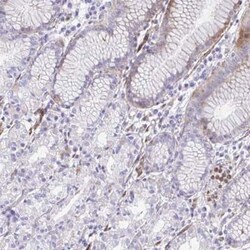

Cystatin B/Stefin B Antibody, Novus Biologicals™

Cystatin B/Stefin B Polyclonal antibody specifically detects Cystatin B/Stefin B in Human samples. It is validated for Immunohistochemistry, Immunohistochemistry (Paraffin)

| Immunohistochemistry 1:50 - 1:200, Immunohistochemistry-Paraffin 1:50 - 1:200 | |